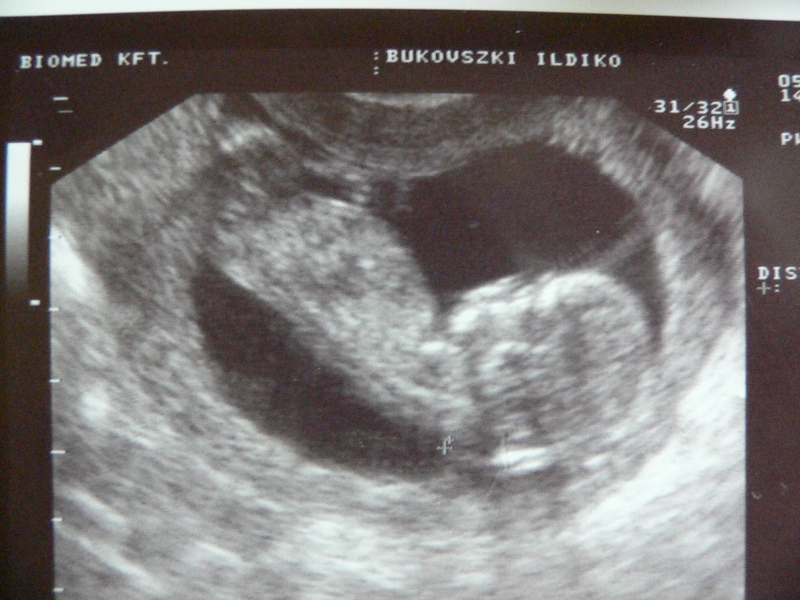

| 12. heti ultrahang. 6,5 cm.

láb, test, fej, kezek láthatóak. |